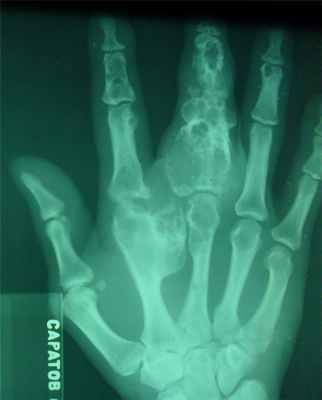

- поражаются фаланги, пястные, плюсневые, реже запястные кости, отростки позвонков, передние концы верхних ребер, тазовый скелет, грудина и весьма редко – длинные трубчатые периферические кости,

- в малых цилиндрических костях хондромы гнездятся в диафизах и эпифизах, в больших трубчатых – только в метафизарных костях,

- как правило хрящевые опухоли множественны и чаще всего наблюдаются в числе одного или нескольких на фалангах рук и пястных костях,

- чаще процесс двусторонний, но не симметричный.

- опухоли шарообразны или овальны, расположены то центрально и вздувают кость изнутри, то эксцентрично и более поверхностно и связаны только с корковым веществом кости,

- опухоль состоит из прозрачного, хрящевого фона на котором видны островки, точечки из извести или костного вещества,

- наружные контуры гладкие и при доброкачественном течении не прерываются,

- на месте слияния опухолевых шаров костная перегородка иногда толстая, в других случаях истончена или отсутствует,

- при поражении эпифизарных хрящей приходится видеть торможение роста кости в длину или ее искривлении,

- нередко центрально расположенная хондрома осложняется патологическим переломом,

- корковый слой неравномерен и местами утолщен,

- при хондроме поверхность кости шероховата.